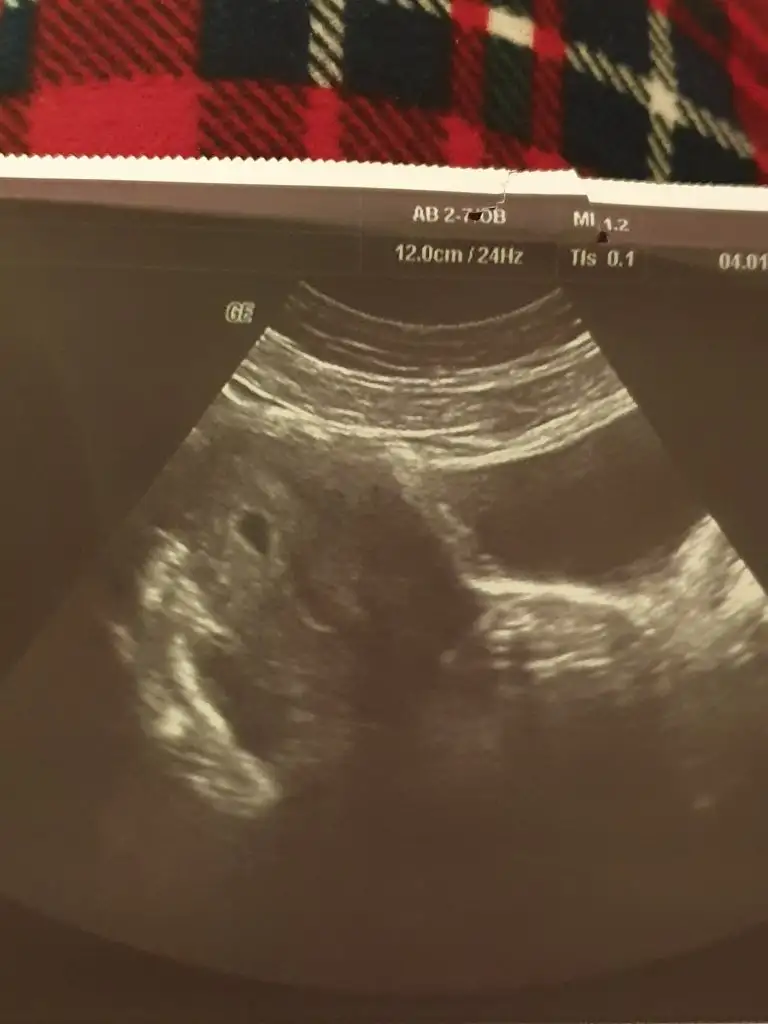

Benim 25 aralık bat di 2 ocakta kese gözüktü ordan hesapla kuzumAa oyle mi maşallahpeki ne kadar zamanda keseyi görecek oluyorsunuz 2 hafta mı

Tamam şimdi kafamda oturmaya başladı doktorum rahmimin çok güzel kalinlastigini söyledi 12 Ocak kontrol 24 Ocak kese görme, gidip sürekli kan verme damarlarına yazık dedi ama ben dinler miyim asla, yarın kan vericem hahahaBenim 25 aralık bat di 2 ocakta kese gözüktü ordan hesapla kuzum

Yine 3 den fazla vermene gerek yok bence 2 günde bir 3 kere verip 2 katına çıktığını gor çünkü her sonuc çıkana kadar stres yapiyosun bu da benim minikTamam şimdi kafamda oturmaya başladı doktorum rahmimin çok güzel kalinlastigini söyledi 12 Ocak kontrol 24 Ocak kese görme, gidip sürekli kan verme damarlarına yazık dedi ama ben dinler miyim asla, yarın kan vericem hahaha

Ayyy masallah Allah kucağınıza almayı nasip etsinYine 3 den fazla vermene gerek yok bence 2 günde bir 3 kere verip 2 katına çıktığını gor çünkü her sonuc çıkana kadar stres yapiyosun bu da benim minik

Hayir daha bulantim baslamadi dun biraz endişelenip dr a gitmiştik bakıp 5+2 haftalık dediBulantı başladı mı peki